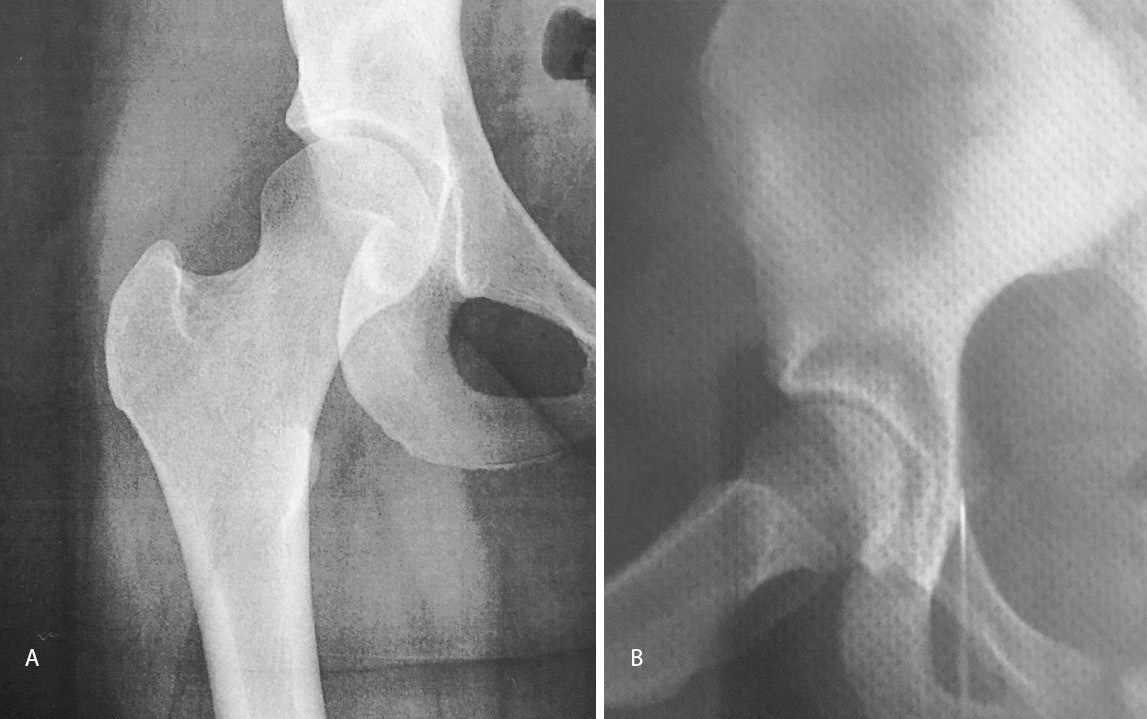

El estudio de imagen mostraba una ausencia de deformidad ósea y no se apreciaron lesiones en la radiografía ni la artrorresonancia (Figuras 1 y 2). El ángulo alfa en la imagen axial izquierda era de 49,6°, mientras que el ángulo de cobertura acetabular de Wiberg era de 34,6°.

Las pruebas de imagen no muestran alteraciones en forma de deformidad de tipo CAM ni PINCER (tanto en radiografías como en resonancia). El ángulo alfa en la proyección axial era de 38,2° y el ángulo Wiberg de 34,5° (Figura 5). Asimismo, el estudio mediante artrorresonancia no evidenció lesiones de labrum ni deformidades del tipo AFA (Figura 6).